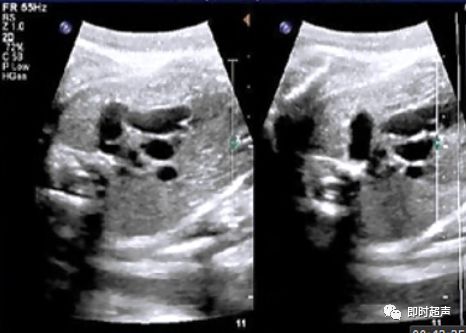

晚孕期胎儿右心扩大的鉴别诊断

- 晚孕期常可观察到胎儿右心比左心大,这常常会造成检查医生的担忧。

- 一般而言,晚孕期胎儿右心就会比左心稍大,这主要是由于胎儿肺循环阻力升高的原因,所以只是右心稍大,大可不必紧张。

- 但如果是右心明显比左心大,那我们就要仔细甄别

- 晚孕期导致胎儿右心扩大的疾病有:妊娠糖尿病、胎儿心脏畸形、胎儿心肌疾病(心肌致密化不全,心内膜弹力纤维增生症)等。

- 如果没有其它病因而仅仅是动脉导管瘤或妊娠糖尿病的话,那么胎儿预后基本良好。

- 如果有胎儿畸形则需明确是何种畸形,再判断预后。